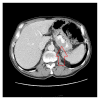

We report a case of a 70-year-old man, with a status after aortic valve replacement, who presented with melena and hypotension. On physical examination, he was hypotensive, but he responded to resuscitation. Esophagogastroduodenoscopy revealed a submucosal mass in the gastric fundus. Imaging of the chest, abdomen, and pelvis showed no evidence of local or distant metastasis. He underwent a partial diaphragmatic resection, gastrectomy, lymphadenectomy, and Roux-en-Y esophagojejunostomy. Pathology showed a gastric squamous cell carcinoma (SCC) invading the diaphragm, with negative margins of resection, and one positive perigastric lymph node. He received chemoradiation, but the patient expired 27 months after surgery.